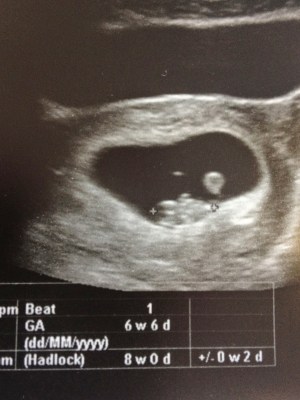

Henry as a yolk sac and fetal pole 🙂